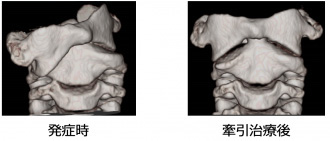

環軸椎回旋位固定

炎症や軽微な外傷をきっかけに、環椎(第1頚椎)と軸椎(第2頚椎)がずれて固定されて しまう疾患。早期治療が重要で、まずネックカラー固定で経過をみますが、改善しない場合 には入院して牽引治療を行います。それでも改善しない場合はハローベスト固定や手術が必要になることがあります。